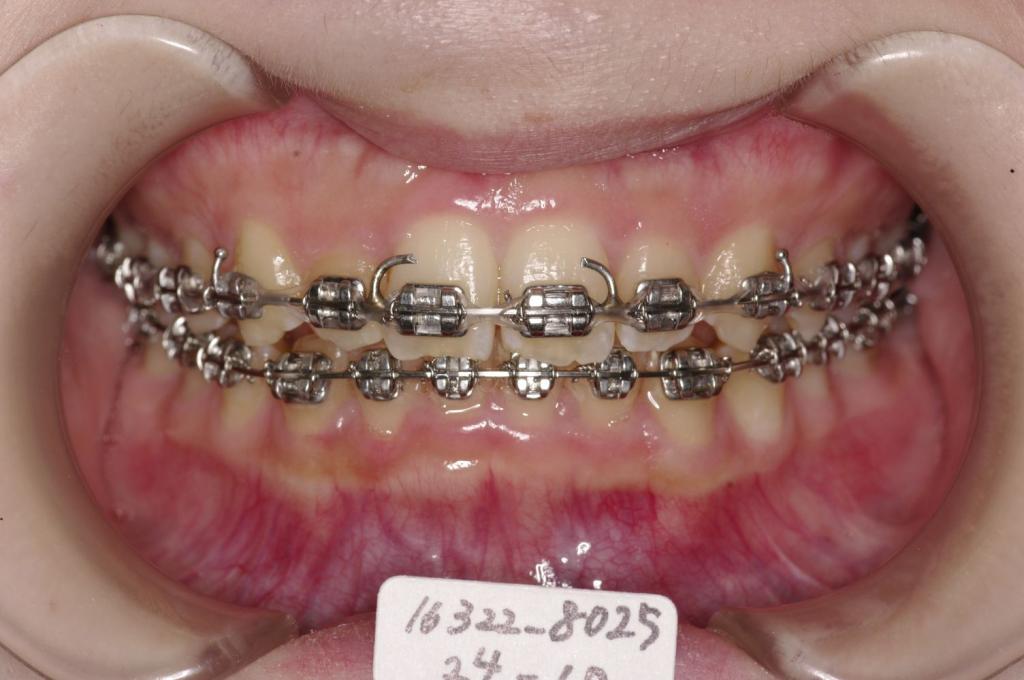

装置の種類及び治療法 診断:叢生

治療方法および装置:マルチブラケット装置

High pull J-hook headgear

外科的矯正手術(健康保険適用)

抜歯:非抜歯

欠損歯:右上8 /左上8

右下8 /左下8

治療期間:11ヶ月

装置写真

治療前

歯並び・咬み合わせ・八重歯・乱杭歯の矯正治療前口内写真NO.1228